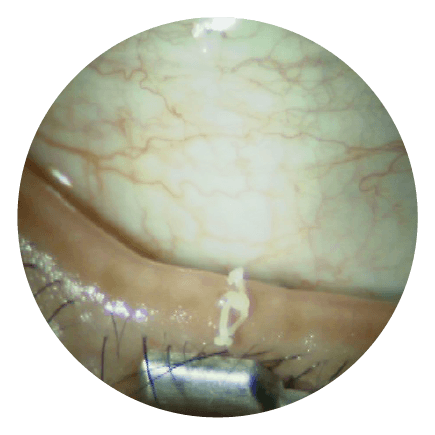

04 圧出前の下眼瞼の様子

マイボーム腺機能不全の部分が盛り上がっています

06 圧出され汚れた脂分

詰まっていた脂分が出てきます